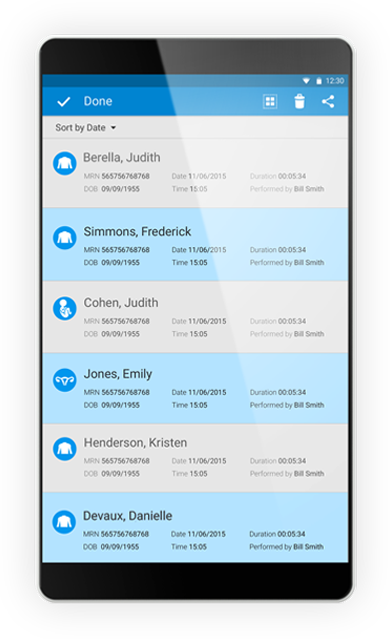

Store and review patient exams and images right from your compatible smartphone or android device. With the ability to share results by email, DICOM, or to a shared network, Lumify enables you to easily collaborate and manage images both on and off your portable MSK ultrasound device.